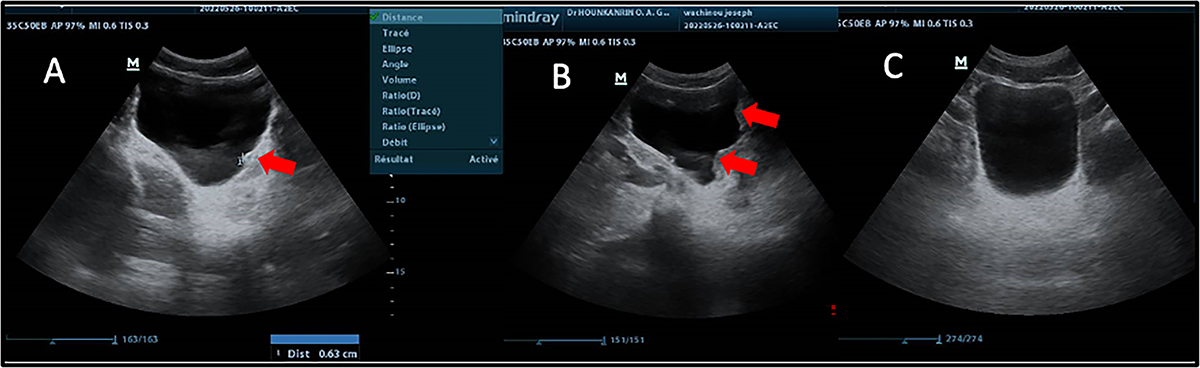

Ultrasound images showing some lesions observed in the bladder of patients with (Sh+) or without (Sh−) S. haematobium infection. A: Bladder of irregular shape and thickened wall (red arrow); B: Bladder of irregular shape with pseudopolyps (red arrow); C: Normal bladder; M: Male patient.